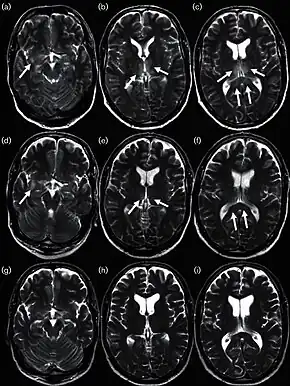

Neurological

In some cases, an autoimmune response to an influenza infection may contribute to the development of Guillain–Barré syndrome.[171] However, as many other infections can increase the risk of this disease, influenza may only be an important cause during epidemics.[171][172] This syndrome has been believed to also be a rare side effect of influenza vaccines. One review gives an incidence of about one case per million vaccinations.[173] Getting infected by influenza itself increases both the risk of death (up to 1 in 10,000) and increases the risk of developing GBS to a much higher level than the highest level of suspected vaccine involvement (approx. 10 times higher by recent estimates).[171][174]

According to the Centers for Disease Control and Prevention (CDC), "Children of any age with neurologic conditions are more likely than other children to become very sick if they get the flu. Flu complications may vary and for some children, can include pneumonia and even death."[175]

Neurological conditions can include:

- Disorders of the brain and spinal cord

- Cerebral palsy

- Epilepsy (seizure disorders)

- Stroke

- Intellectual disability

- Moderate to severe developmental delay

- Muscular dystrophy

- Spinal cord injury

These conditions can impair coughing, swallowing, clearing the airways, and in the worst cases, breathing. Therefore, they worsen the flu symptoms.[175]